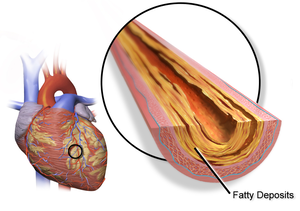

إن العلاج طويل الأجل بالهورمونات قد يقي من العديد من الأمراض الشائعة بين النساء المتقدمات في السن. على سبيل المثال، قد يقي الإستروجين من مرض القلب وتخلخل العظام، وهو فقدان أنسجة العظام الذي يجعلها معرضة للكسر.